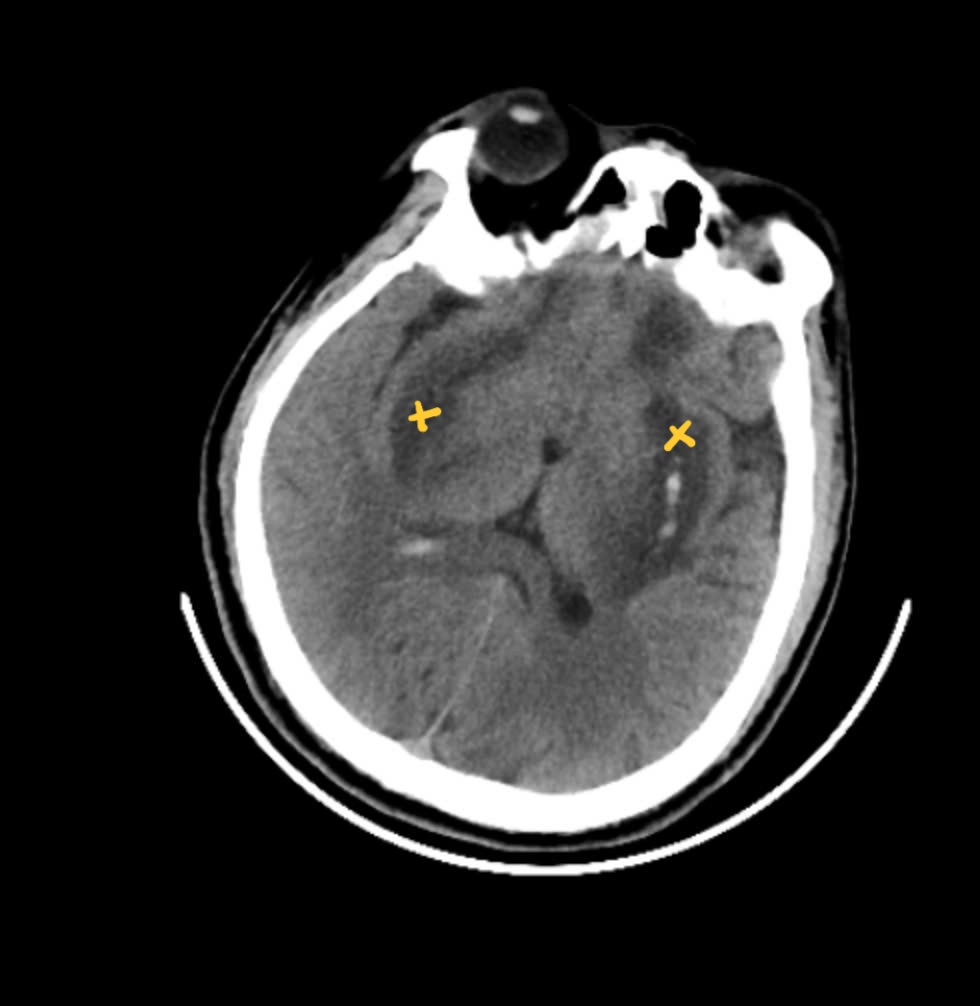

Hình ảnh chụp MRI não bệnh nhân: nhân bèo hai bên não bị hoại tử và chảy máu (các vùng đánh dấu)

Trung tâm Chống độc, Bệnh viện Bạch Mai tiếp nhận người đàn ông 55 tuổi, (Hoàng Mai, Hà Nội) trong tình trạng hôn mê, suy hô hấp, nhiễm toan chuyển hóa nặng. Xét nghiệm trong máu có chứa nồng độ cồn công nghiệp methanol cao 116,63 mg/dL và kết quả chụp MRI não có xuất hiện tổn thương hoại tử nhân bèo và biến chứng chảy máu não. Điều đáng nói bệnh nhân không có tiền sử nghiện rượu, cơ thể khoẻ mạnh và thường chỉ có thói quen dùng cồn để xúc miệng, ngậm chữa đau răng.

Tại thời điểm nhập viện ban đầu, ngoài những triệu chứng kể trên người bệnh tỉnh táo, các chỉ số sinh tồn, tim phổi bình thường, không rối loạn cảm giác. Chụp MRI não có xuất hiện ổ nhồi máu nhỏ nhân bèo trái. Xét nghiệm khí máu các chỉ số cho thấy sự bất thường. Tiếp đó, bệnh nhân giảm dần ý thức, đồng tử giãn, suy hô hấp, hôn mê phải đặt nội khí quản thở máy. Nghi ngờ ngộ độc methanol nên ngay trong ngày, bệnh nhân được chuyển tới Trung tâm Chống độc để đánh giá, xử trí, lọc máu.